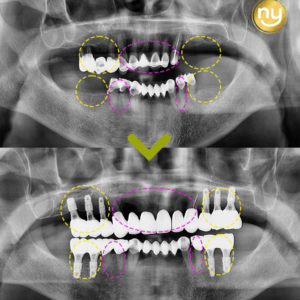

처음 본원에 내원하셔서 찍은 파노라마 사진입니다.

전체적으로 잇몸뼈의 소실이 심하고

하악의 브릿지와 크라운을 수복한 치아들도

염증이 발생되어 있는 것을 보실 수 있는데요.

염증과 치주 질환으로 인해 치아 흔들림이 심해 상악 송곳니 2개와

작은 어금니 1개를 제외하고는 살릴 수 있는 치아가 없어서

나머지 치아들은 발치를 진행하기로 했습니다.

상악 앞니 들은 살려서 사용이 가능한 3개의 치아를 이용하여

브릿지를 제작하여 전치부의 기능을 회복하였는데요.

상악 구치부의 경우 오른쪽 3개, 왼쪽 2개를 식립하여

어금니의 역할을 수행할 수 있도록 제작해드렸는데요.

상악의 경우 잇몸뼈가 많이 소실되어 있는 상태라

길이가 짧은 임플란트를 사용하여 식립하였고

별도의 뼈이식 없이 임플란트 식립을 진행하였습니다.

하악에는 전치부 2개, 구치부 각 오른쪽 4개,

왼쪽 3개의 임플란트 식립으로 총 12개 치아의 기능을 회복하였습니다.

하악 오른쪽 뒤 큰 어금니와 왼쪽 송곳니 쪽에는 염증이 심했던 상태라

임플란트의 식립이 어려워, 큰 어금니 1개를 제외하고

위아래 모두 12개씩 총 24개의 치아 기능을 회복하였습니다.